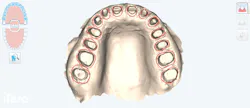

Intraoral digital scans (figure 4) were obtained for comprehensive evaluation of interocclusal relationships. In the sagittal view, the patient exhibits a class I molar relationship on the left and a class II relationship on the right. This asymmetry is clinically significant, as the posteriorly positioned right mandible (class II side) has the potential to negatively influence facial symmetry and esthetics if not addressed in the treatment planning phase. Proper recognition of this discrepancy was essential in guiding the development of a full-face rehabilitative protocol and ensuring both functional stability and esthetic balance in the final smile design.

Transverse evaluation revealed significant occlusal and lingual wear patterns, with malposition of teeth relative to the ideal ovoid arch form. Notably, tooth no. 7 was rotated facially, compromising arch symmetry. The patient was also missing teeth nos. 18 and 28. The absence of no. 18 resulted in hypereruption of no. 15 into an open interocclusal space, while the loss of no. 28 contributed to the upper and lower midlines being noncongruent.

From the anterior perspective, the patient presented with a deep overbite, covering approximately 75% of the mandibular anterior dentition, coupled with insufficient overjet. This functional imbalance exacerbated the patient’s parafunctional bruxism and contributed to generalized incisal and occlusal wear. The maxillary midline was also deviated, failing to harmonize with the patient’s facial esthetics.